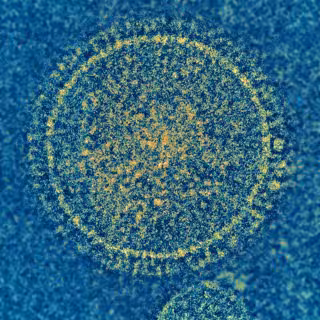

¿Cómo interactúan los anticuerpos con un virus respiratorio?

Virus sincitial respiratorio

El equipo de investigación también usó microscopía electrónica para visualizar las interacciones anticuerpo-virus. Este trabajo reveló que 17E10 se une a la proteína F en un ángulo mucho más pronunciado que los otros tres anticuerpos. El inusual ángulo podría estar directamente relacionado con la capacidad de 17E10 para neutralizar tanto RSV como hMPV.